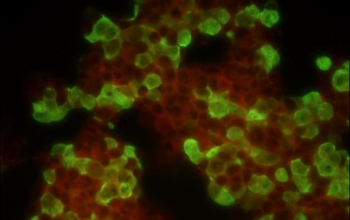

Nhờ sử dụng hệ quang học Infinity plan achromatic objectives, MF31 cho hình ảnh sắc nét đến từng chi tiết nhỏ nhất. Đặc biệt, độ chính xác màu sắc và độ tương phản cao giúp người quan sát nhận diện mẫu vật dễ dàng hơn, ngay cả với những mẫu có độ phát huỳnh quang yếu.

- Bộ lọc huỳnh quang: Blue, Green, UV,… tùy theo ứng dụng

- Quan sát mô bệnh học và tế bào học

- Kiểm nghiệm chất lượng mẫu sinh học